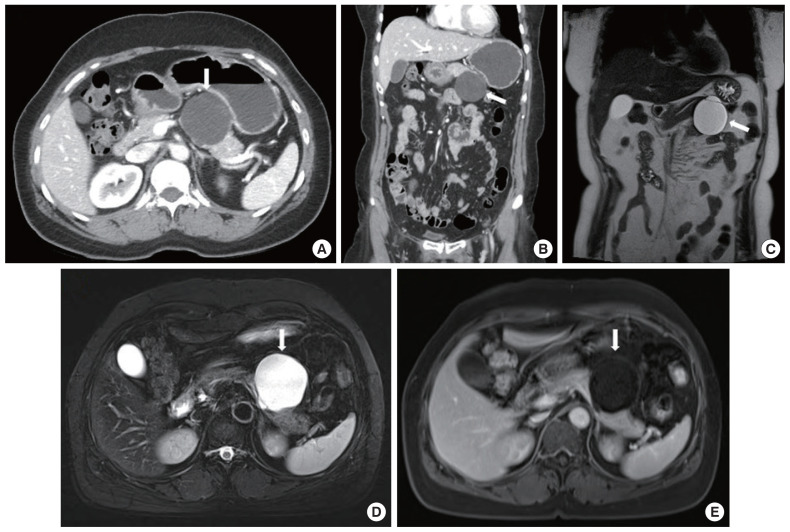

胰腺远端切除加脾切除术被认为是治疗胰腺尾癌和胰体癌的标准手术。不过,良性或低度恶性肿瘤(包括粘液性囊腺瘤和导管内乳头状粘液瘤)可选择脾切除术。如果进行了边界病变的保脾胰腺远端切除术(SPDP),术后病理结果确诊为胰腺癌,如果是 R0 切除术,是否有必要进行额外的脾切除术仍值得商榷。作者希望报告两例在 SPDP 术后病理诊断为胰腺癌的临床病例,在观察期间没有进行额外的脾切除术。

Distal pancreatectomy with splenectomy is considered the standard operation for pancreas tail and body cancer. However, splenectomy may be option for benign or low-grade malignant tumors including mucinous cystadenoma and intraductal papillary mucinous neoplasm. If spleen-preserving distal pancreatectomy (SPDP) with borderline lesion is performed and pancreas cancer is diagnosed on postoperative pathologic finding, if it is R0 resection, the necessity of additional splenectomy remains questionable. The authors would like report two clinical cases diagnosed as pancreatic cancer on postoperative pathology after SPDP and under observation without additional splenectomy.